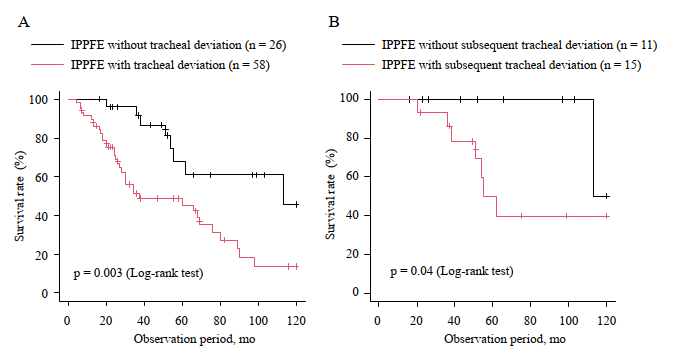

- 気管偏位なし群より生存率が不良であった(ログランク検定 p = 0.003)。

診断時に気管偏位がない26例のうち15例(57.8%)が経過中に気管偏位を発症し、これも予後不良と関連した(ログランク検定 p = 0.04)。

3) 合併症(気胸)と予後に直結していた

- 診断後の気胸:気管偏位あり 44.8% vs なし 19.2%

- 生存:気管偏位あり群の方が有意に不良(log-rank p=0.003)

- さらに、診断時に偏位がなかった人も、経過で偏位が出現した群は予後不良(p=0.04)